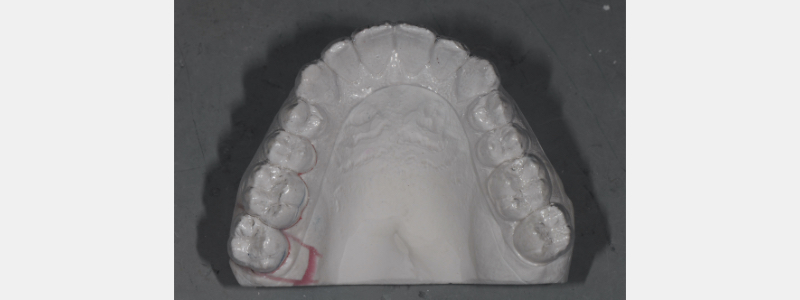

The technique applied to these situations is very simple and easily managed in the dental office (versus dental laboratory collaboration). Once the open contact has been verified, an evaluation and correction of occlusal contact is performed (Fig. 2). Opposing “distal wedging” forces are adjusted and corrected. Elimination of these occlusal contacts is paramount for successful proximal contact management and closure. An alginate impression is obtained and poured in hard stone (die stone).

The contact closure technique can be applied once the poured model is hardened and trimmed. Horizontal parallel lines are scribed on the buccal (and lingual, if desired) aspect of the stone teeth involved in the open contact. Extend the lines at least one tooth forward of the open contact. These lines are used as re-positioning reference points once the die cuts are completed.